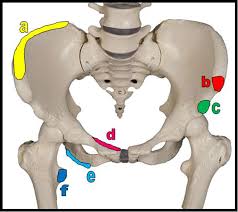

With an avulsion fracture, an injury to the bone occurs near where the bone attaches to a tendon or ligament. Anyone can suffer an avulsion fracture of the ankle, but athletes and children are more prone to them than the rest of us. This happens when a muscle or tendon connected to the hip bone suddenly tightens so hard that it pulls off part of the bone. Ebraheim's educational animated video describes the condition of avulsion fractures around the hip in adolescence. An avulsion fracture occurs when a small chunk of bone attached to a tendon or the hip, elbow and ankle are the most common locations for avulsion fractures in the young athlete. If you think you've fractured your hip, you'll need to go to hospital as soon as possible. In acute avulsion fractures, there is usually a clear preceding traumatic incident. When to seek medical help. The causes of hip fracture are very different in young and elderly patients. With age, the bones can become weak and brittle. Other causes include cancer and injury. They usually happen when a bone is moving one way, and a tendon or ligament is suddenly pulled the opposite way. Hip apophyseal injuries in young athletes are a fairly rare problem, and often go unrecognized by health professionals.

Pain in the hip area may be referred from the knee joint or from structures in the inguinal canal, testis (including torsion) and lower abdomen, or from the lower back. Teenagers are more likely to have this injury than younger children. The causes of hip fracture are very different in young and elderly patients. Other causes include cancer and injury. Hip fracture occurs in approximately 341,000 persons in the united states each year. Read about causes, treatment options, available mobility devices, tips for recovery, and more. This happens when a muscle or tendon connected to the hip bone suddenly tightens so hard that it pulls off part of the bone. In acute avulsion fractures, there is usually a clear preceding traumatic incident. A hip fracture is a break in the bones of your hip. A hip fracture is a common injury, especially in people with osteoporosis. I was doing high jump and twisted my body and in the process my muscle ripped my growth bone off. A broken hip in older people is often partly the result of weakening bones from osteoporosis. This most commonly occurs at the ischial tuberosity where the hamstrings attach, or the iliac pain at the bony part on the front of the hip may be an anterior superior iliac spine avulsion fracture.